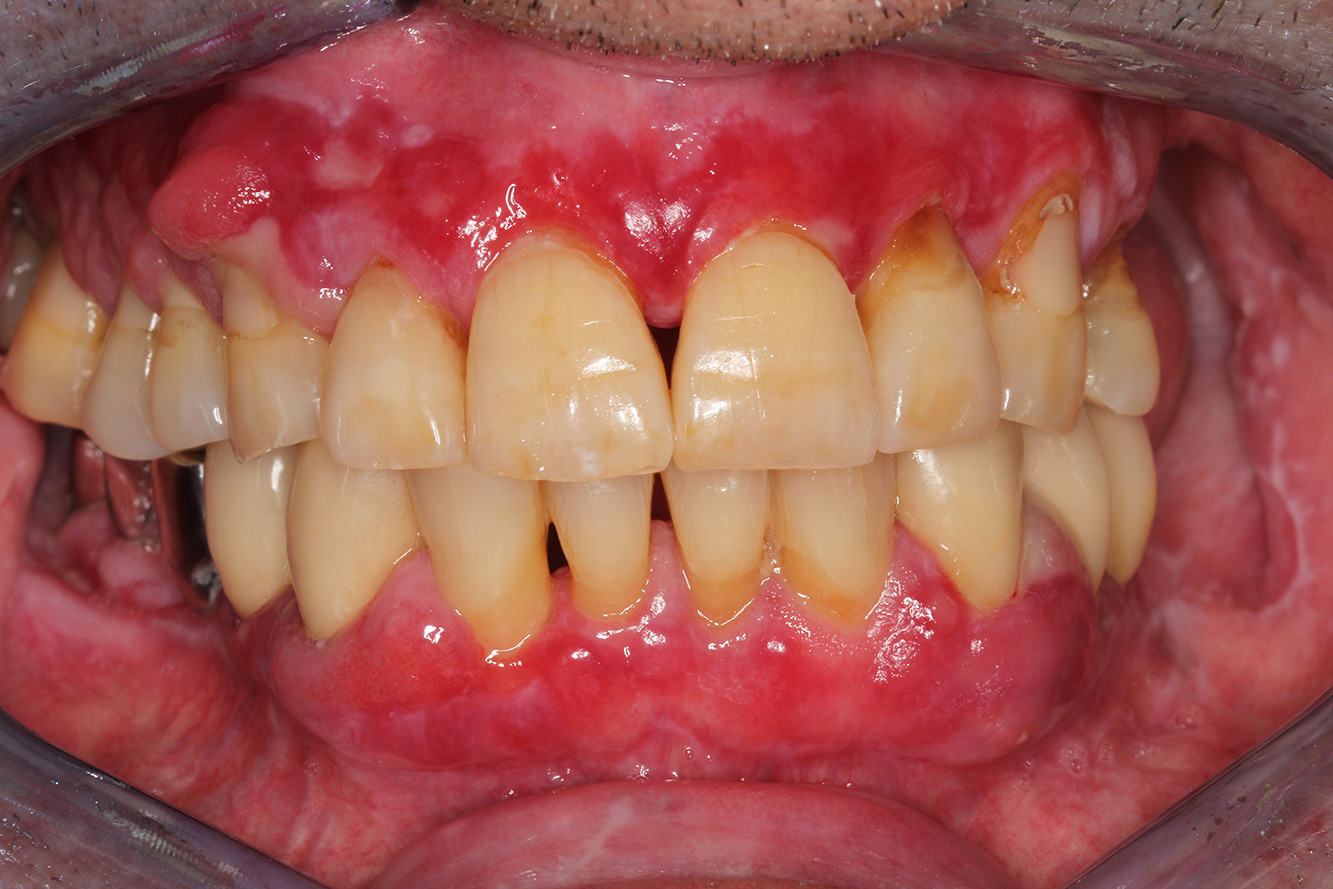

Ein 71-jähriger Patient mit Z.n. Nierentransplantation und Hypertonie (Bluthochdruck) stellt sich vor. Bedingt durch die Krankengeschichte ist eine Dauermedikation mit Cyclosporin, zur Unterdrückung der Immunabwehr, und Amlodipin, zur Blutdrucksenkung, erforderlich. Außerdem berichtet der Patient über empfindliches Zahnfleisch und Zahnfleischbluten. Aus mundgesundheitlicher Sicht zeigt sich ein saniertes Gebiss mit acht fehlenden Zähnen, ausgeprägte Gingivawucherungen, eine Parodontitis Stadium II, Grad B mit aktiven Taschen und eine initiale Wurzelkaries an Zahn 22. In der Kariesrisikoabschätzung wird ein mittleres Kariesrisiko (API 60) festgestellt. Für die Prophylaxesitzung lassen sich folgende Behandlungsempfehlungen ableiten.

Anhand der Krankengeschichte lässt sich ein besonderes Komplikationsrisiko erkennen. Aufgrund des Nierentransplantats ist der Patient immunsupprimiert (Cyclosporin), verfügt also über ein geschwächtes Immunsystem und benötigt eine Infektionsprophylaxe (Empfehlung: 2 g Amoxicillin als Antibiotikum 1h vor Sitzung). Gleichzeitig birgt die Dauermedikation des Patienten ein erhöhtes Erkrankungsrisiko, da die festgestellten Gingivawucherungen medikamentenassoziiert sind (21).

Besonders im Bereich der Motivation und Instruktion muss auf die Situation des Patienten eingegangen werden. Durch die Gingivawucherungen gestaltet sich die häusliche Mundhygiene schwierig. Die erhöhte Anfälligkeit für Infektionen sowie das Fortschreiten und die Neuentstehung der Wucherungen (22) sollte auf Augenhöhe thematisiert werden. Gleichzeitig müssen die individuell auf den Bedarf abgestimmten Hygienetechniken vermittelt werden.